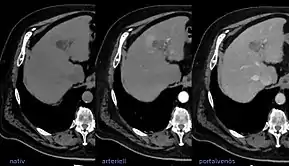

![]() LIRADS classification is applied to multi-phase contrast-enhanced CT or MRI scans in people with certain chronic liver diseases. | |